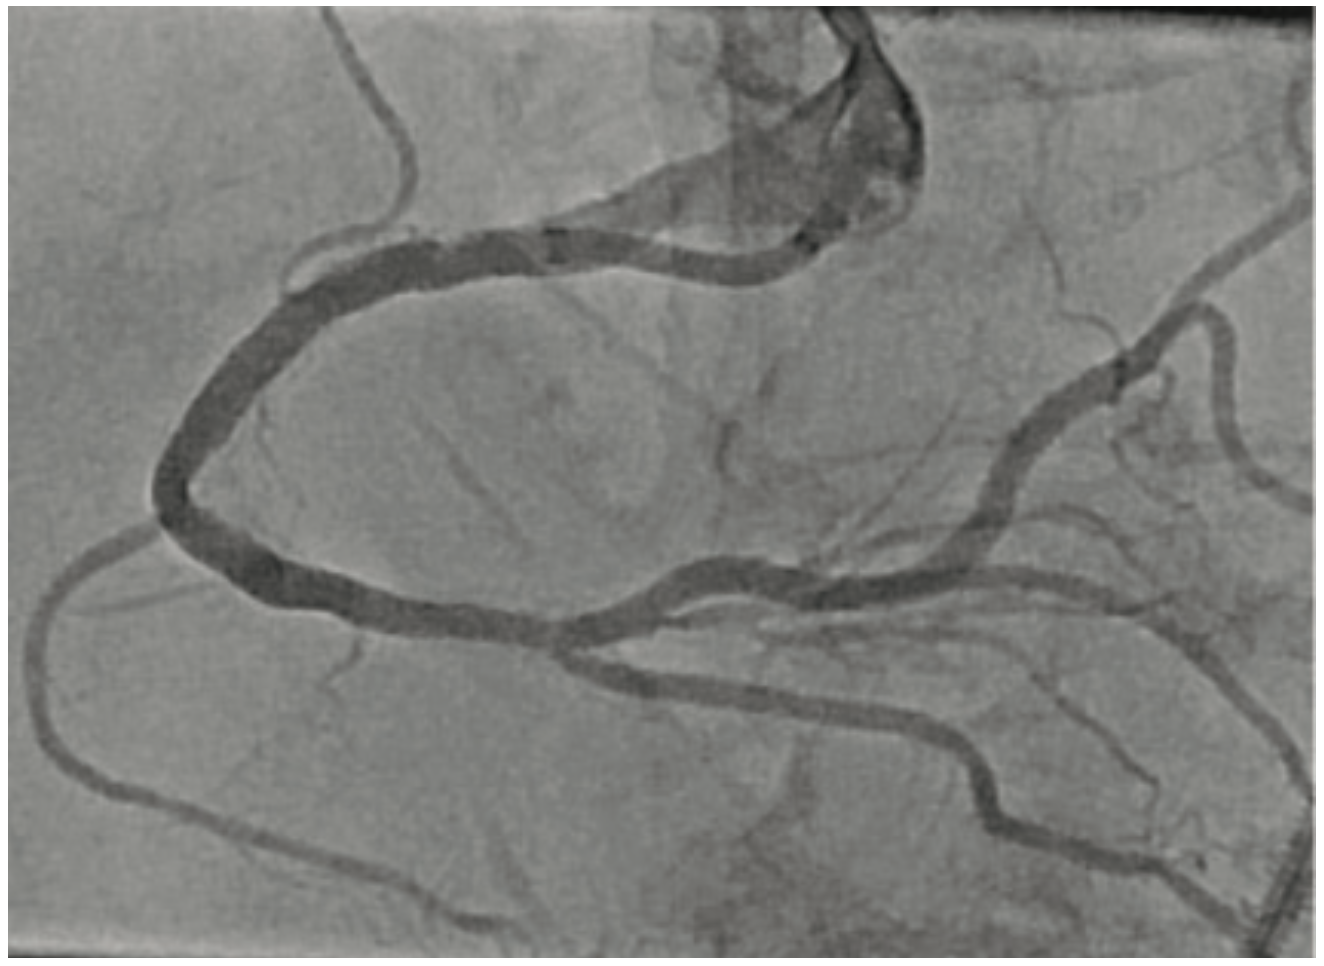

Intravascular lithotripsy (IVL) has been shown to be both safe and effective in the treatment of calcified coronary artery disease, with low rates of device-related adverse events, as shown in the DISRUPT CAD study series.3-6 Certainly, any device that may assuage operator concerns regarding complications when treating complex lesions could translate to an increase in use of calcium modification where indicated. Since we know that inadequate lesion preparation may lead to higher rates of in-stent restenosis and stent thrombosis, it follows that IVL could help lower suboptimal PCI rates in both men and women.

Small retrospective studies have suggested that women may be at an increased risk for procedural complications after atherectomy. Procedural complications are often related to vascular injury during plaque modification. As post-menopausal women have been shown to have increased arterial stiffness, less vessel compliance, and increased vascular fragility, it is not surprising that these factors, in conjunction with smaller coronary artery size, could lead to higher rates of coronary perforation and dissection during treatment of calcified plaque. The sex-specific analysis of the DISRUPT CAD series of studies presented at SCAI 2022 demonstrated that there was no difference in angiographic complications, successful stent delivery, and 30-day adverse cardiovascular events between men and women.7 These are certainly reassuring data, which suggest that the possible safety signals seen in women treated with atherectomy may not be present with IVL.